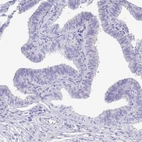

Immunohistochemistry analysis in human pancreas and fallopian tube tissues using HPA006641 antibody. Corresponding SCGN RNA-seq data are presented for the same tissues.